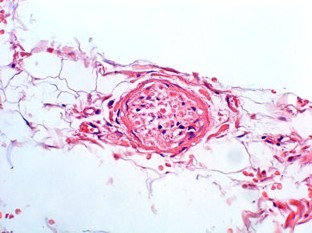

Ionizing radiation as a cancer therapy is associated with a variety of undesirable side effects. Consequently, radiotherapy can negatively affect neuromuscular function. Clinical observations have identified problems with swallowing and voice function. Our study aims to evaluate the impact of radiotherapy on laryngeal soft tissues using image analysis to quantify its effect on the structure of the vocalis and thyroarytenoid muscles. Case control study, retrospective analysis. We collected total laryngectomy specimens from six patients with persistent or recurrent cancer who had received preoperative radiotherapy (60–66 Gy). The control group consisted of total laryngectomy specimens from six patients who underwent surgery as primary treatment. Sampling of the specimens only included non-cancerous laryngeal tissue. Laryngeal histological slices were evaluated using digital morphometric analysis system. Percentage of fibrosis and density of muscle fibers within the thyroarytenoid muscle were evaluated in both groups. We found no significant quantitative differences in muscle fibrosis (7.92% vs. 7.52%, P > 0.1). Changes were rather qualitative and included changes in the organization of the muscular fibers. A significant reduction in muscle fibers, however, was observed in the samples from irradiated larynges (66.45% vs. 42.03%, P < 0.01). Our analysis suggests that radiotherapy is responsible for a significant reduction in muscle fibers in the thyroarytenoid muscle and that these changes occur during treatment or relatively early after its completion. Loss of muscle mass after irradiation correlates with clinical observations of muscle weakness and decreased function in patients who undergo radiotherapy.

Fig. 3